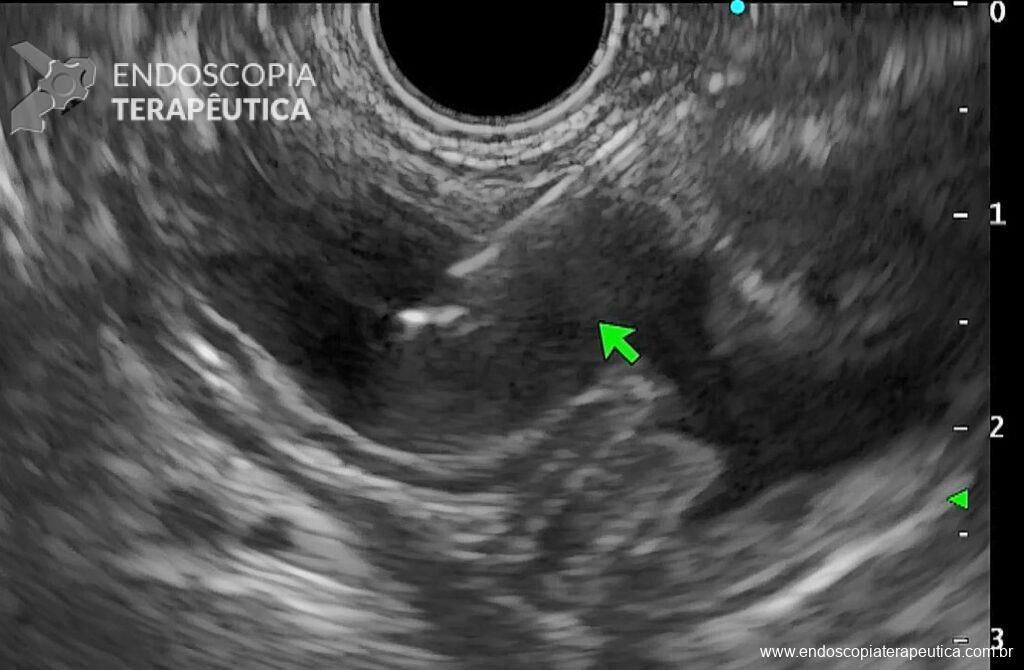

- Em transição esofagogástrica, localizar a borda inferior do fígado e girar sentido horário pela visão ecoendoscópica até localizar a “bolacha do mar”, sand dollar sign, que seria o estômago excluso em sua porção antral (Figura 2);

- Puncionar a porção distal do estômago com agulha FNA de 19G até encostar na parede contralateral e retrair a agulha discretamente para centralizar no lúmen (Figura 3);

- Dica: utilizar o doppler para evitar vasos no trajeto de punção e sangramento desnecessário é essencial.